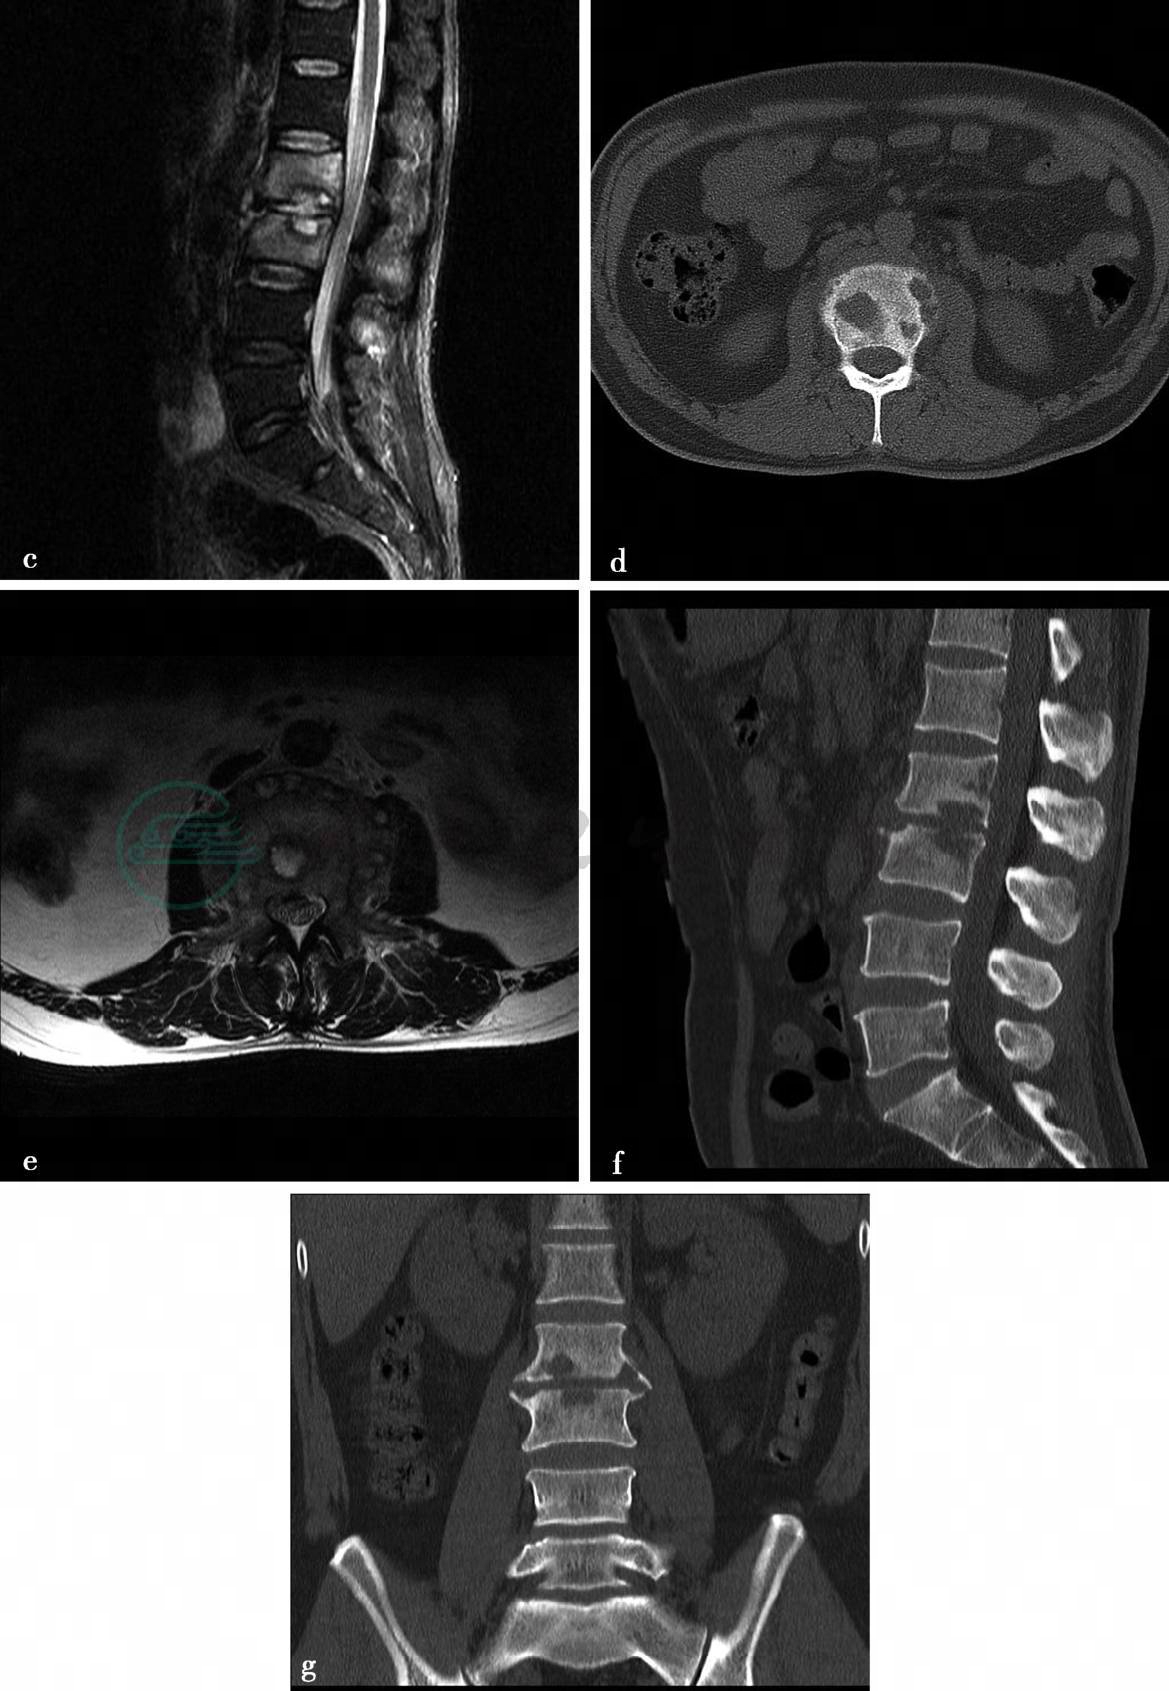

(2)病例5-2-8:

CT平扫及MRI平扫、增强扫描。

图2 d、f、g,CT平扫示矢状面重建图像显示腰椎生理曲度略变直。L2、L3椎体内可见多发斑片状溶骨性骨质破坏,边缘清楚,周围无骨质硬化。L2/3椎间隙变窄,骨性椎管无变窄,椎旁软组织稍肿胀。图2a、b、c,MRI示腰椎生理曲度略变直。L2/3椎间隙变窄。L2、L3椎体相对缘骨性终板骨质破坏。图2b,T1WI呈低信号。图2a,T2WI呈稍高信号,信号不均匀图2c,STIR序列呈高信号。L2、L3椎体在T1WI(图b)上呈均匀低信号,在STIR(图d)上呈均匀高信号。椎旁软组织肿胀,多发小囊状信号影。硬膜囊略受压

(2)病例2,(腰2、3椎体)结核(边缘型)。